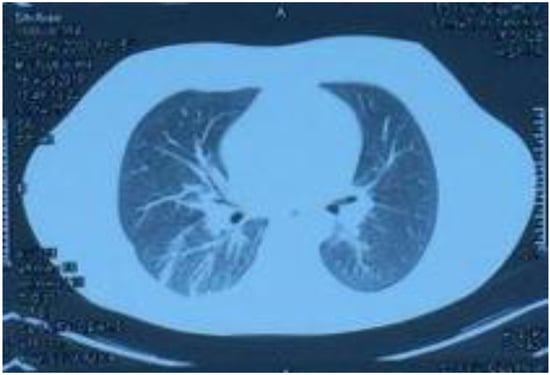

Figure 4.

Lung CT reexamination performed on 1 September 2018, showing symmetrical thorax, increased bilateral lung textures, nodules in the middle lobe of the right lung, and a small amount of high-density shadow in the lower lobe of the right lung, which was significantly smaller than before.

On 1 September, the patient came back to the hospital for routine blood examination as well as liver and kidney function and myocardial damage marker tests. The lung CT reexamination revealed that the thorax was symmetrical, the bilateral lung textures had increased, nodules were observed in the middle of the right lung, and a small amount of high-density shadow was observed in the lower right lung, which was significantly smaller than before. The examination results of the patient had normalized and reached the standard for a clinical cure. Before the submission of this paper, we made a telephone appointment with the patient; the patient was in a complete recovery state, all the examinations were normal, and he could continue to engage in various labor activities.